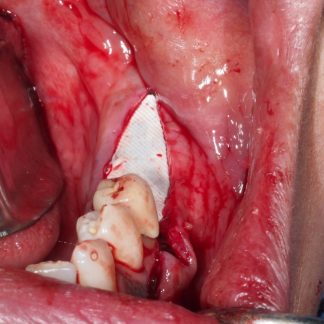

- Colocación de membrana Jason

- Colocación de gránulos de hueso

- Fijación de la membrana con tachuelas